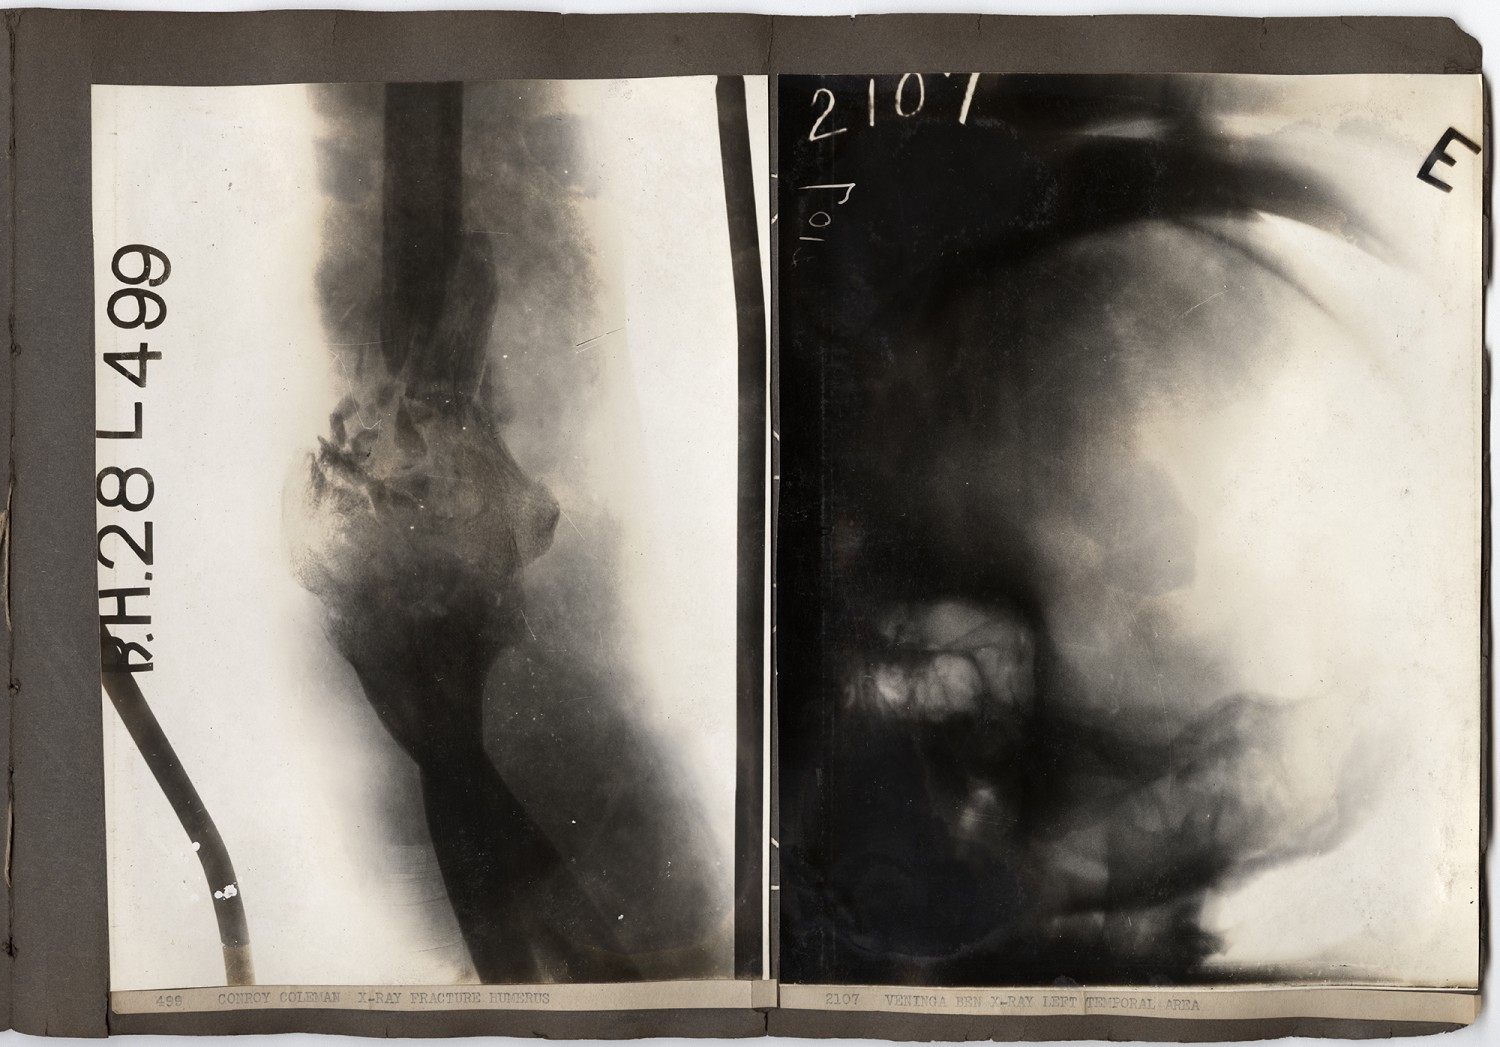

[x-ray, left] 499 CONROY COLEMAN X-RAY, FRACTURE HUMERUS [x-ray, right] 2107 VENINGA BEN X-RAY, LEFT TEMPORAL AREA